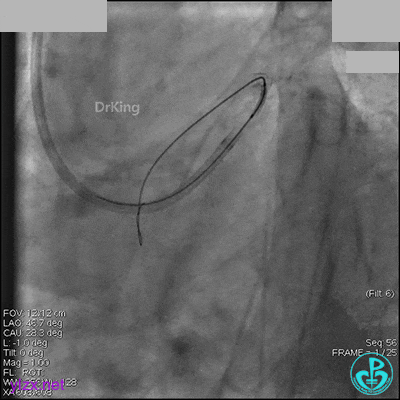

先处理前降支开口严重狭窄并顺利植入前降支到左主干支架。